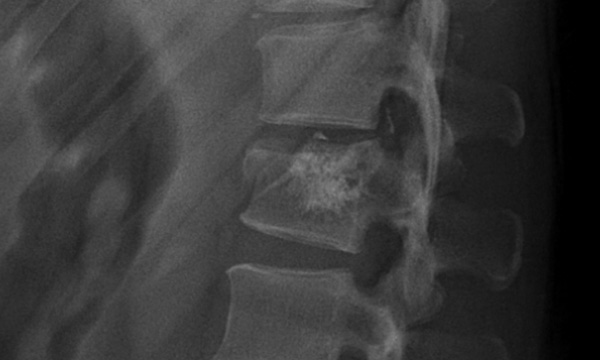

X-ray

X-ray(엑스레이)로 척추뼈가 찌그러진 상태 확인